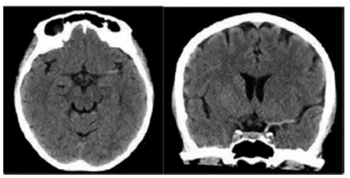

Um paciente do sexo masculino, 63 anos, é trazido ao pronto -socorro pelos familiares, apresentando afasia e diminuição da força no membro superior direito, com início dos sintomas há cerca de 2 horas. Realizou tomografia computadorizada (TC) de crânio cuja imagem está demonstrada a seguir.

(Arquivo pessoal; imagem usada com autorização)